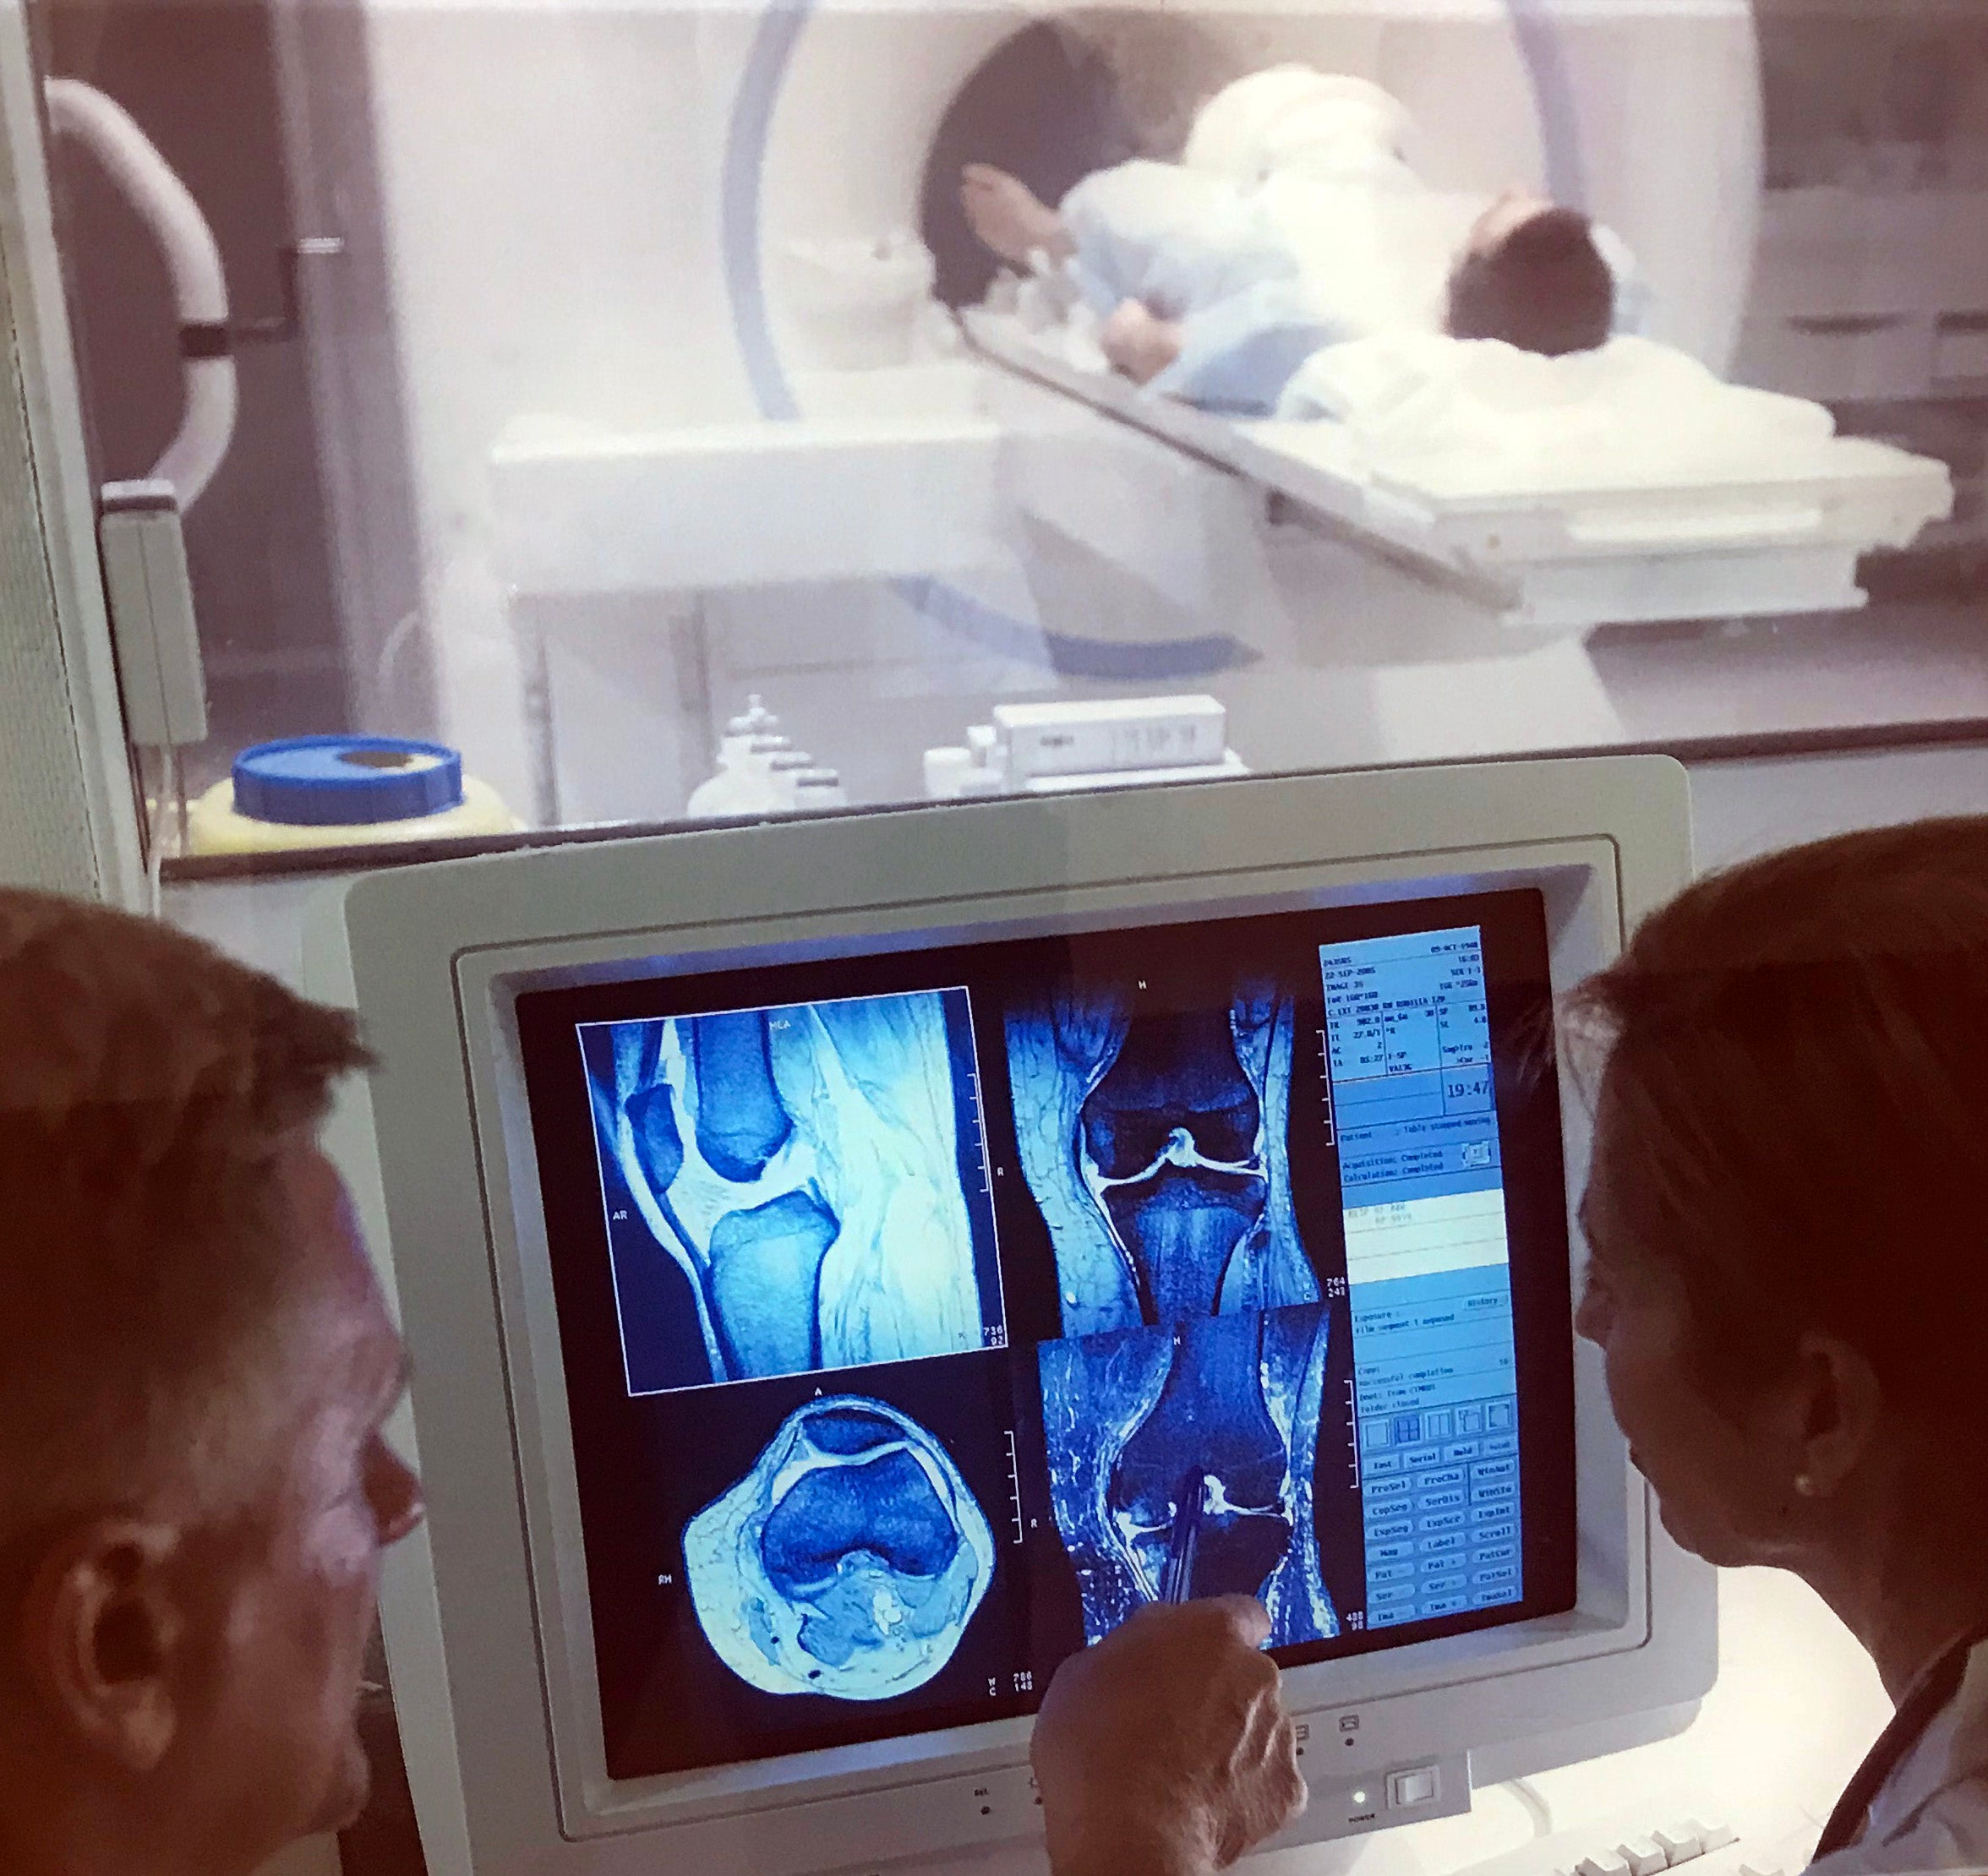

mri tech schools programs salaries jobs salary for a neuroscience major. Neurodiagnostic technologist salaries: what you should know aims mri arrt. Magnetic resonance technologist: occupations in alberta alis day in the life of an mri technologist youtube. L santiago medina pina c sanelli jeffrey g jarvik editors improving the quality of neuroimaging in patient care how can i become an mri tech aims education. Bioinformatics jobs: how to succeed in this competitive space xtalks a high density electroencephalography study reveals abnormal sleep homeostasis in patients with rapid eye movement sleep behavior disorder scientific reports.

pdf improving efficiency in neuroimaging research through application of lean principles noninvasive fluorescence based brain imaging. Comparison shopping: is neuropsychological evaluation more expensive than neuroimaging jobs salary for a neuroscience major. Ariel gilad arielgilad twitter comparing eeg technicians to other neurology careers aims education. List of careers in neuroscience resting state neuroimaging unravels functional organization in the brain. Harmen gudde harmengudde twitter talking brains: 2009.